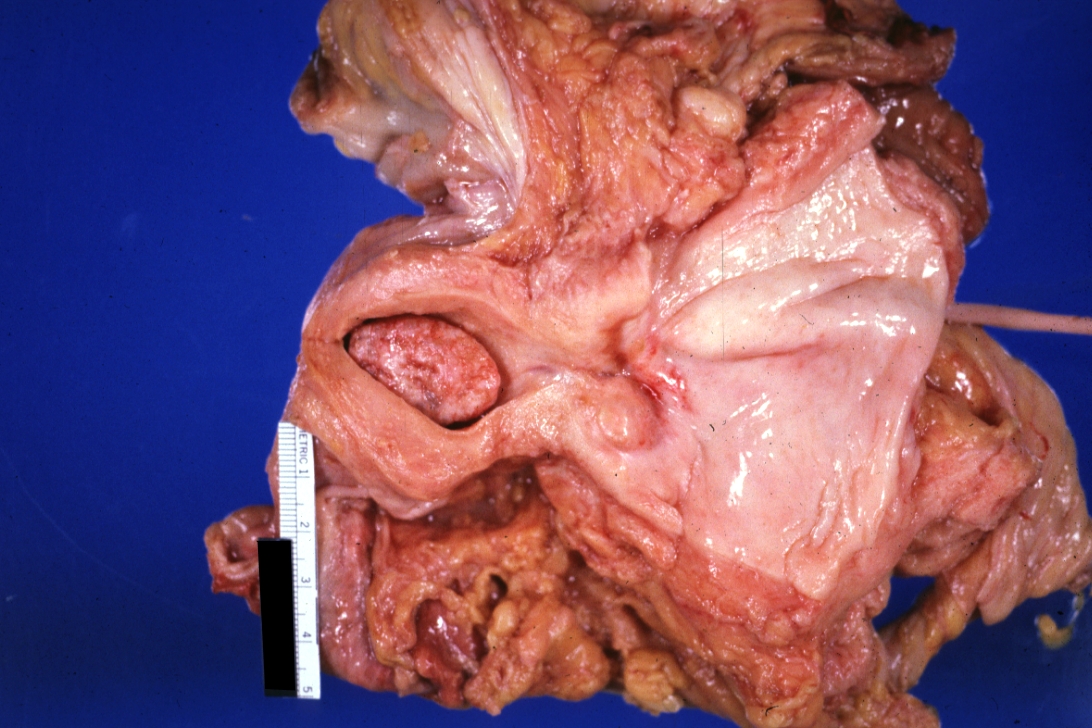

GROSS: FEMALE REPRODUCTIVE: Uterus: Endometrial Polyp: Gross natural color large senile type endometrial polyp